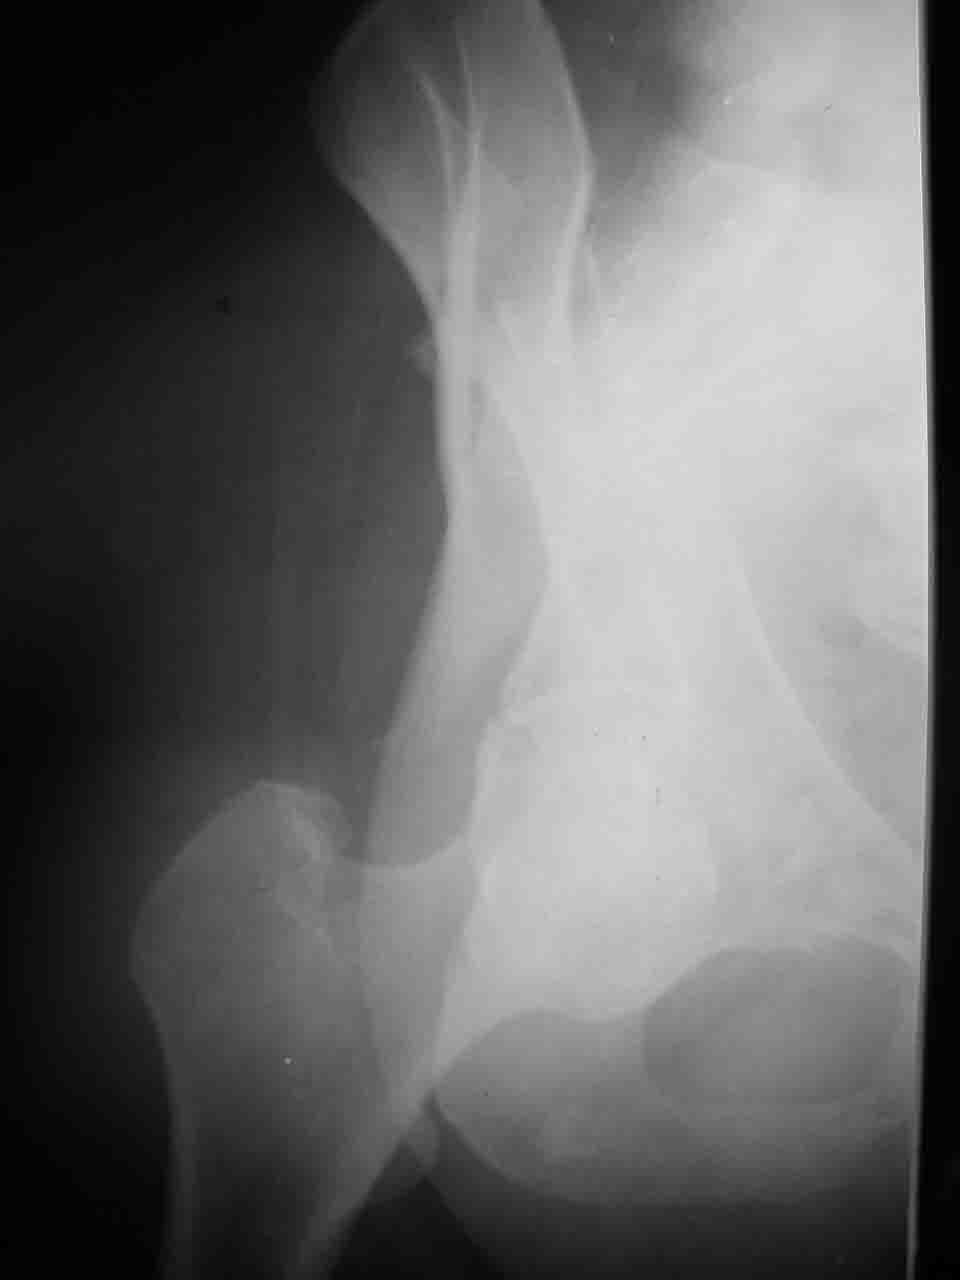

Интерес к реконструкции вертлужной впадины у меня появился довольно-таки давно, но до недавнего времени как-то не ощущалась готовность к практической реализации, а местный подход достаточно консервативен - перелом срастется,

а далее будет видно. Такую точку зрения я не разделяю, поэтому через конференции,ортофорум и свои случаи пытаюсь практически и теоретически *продвинуть* для себя тему реконструкции вертлужной впадины.

Логика подсказывает, что все-таки лучше иметь анатомически полноценную впадину, хотя ранее упоминалось состояние вторичной конгруэнтности и одно наблюдение у меня есть, когда у больного с полностью нарушенной анатомией впадины и подвывихом головки бедра кзади и кверху боли отсутствовали при относительно достаточном для стиля жизни больного объёме движений. Но это только одно наблюдение и кроме перелома впадины у этогобольного была и тяжелая ЧМТ в анамнезе. Основываясь на формулировке структуры ацетабулюм Э. Летурнеля - как перевернутой буквы Y, впадина для полноценной функции сустава должна иметь сферичность, соответствующую размеру головки бедра и если один из компонентов в дефиците, то функциональные последствия рано или поздно проявятся.

Сложностью, ассоциативностью характера перелома, я бы с радостью воспользовался мининвазивной перкутанной фиксацией винтами, но боюсь, что результат был бы ещё хуже, техникой непрямой репозиции перелома не владею, поэтому пытаясь получить анатомичную впадину приходится широко открывать, по крайней мере пока, а дальше буду пытаться уменьшать пространство...

> передним доступом на двухколонный перелом?

Илеофеморальный доступ не совсем передний и сравнительно с илеоингвинальным, и Кохера-Лангенбека открывает весь наружный таз кроме самых передних отделов лонных костей, фиксацию которых я не ставил в задачу. Обширность диссекции, большая длительность операции и более высокий риск гетерооссификации - отрицательные моменты в обмен на возможность легче ориентироваться.